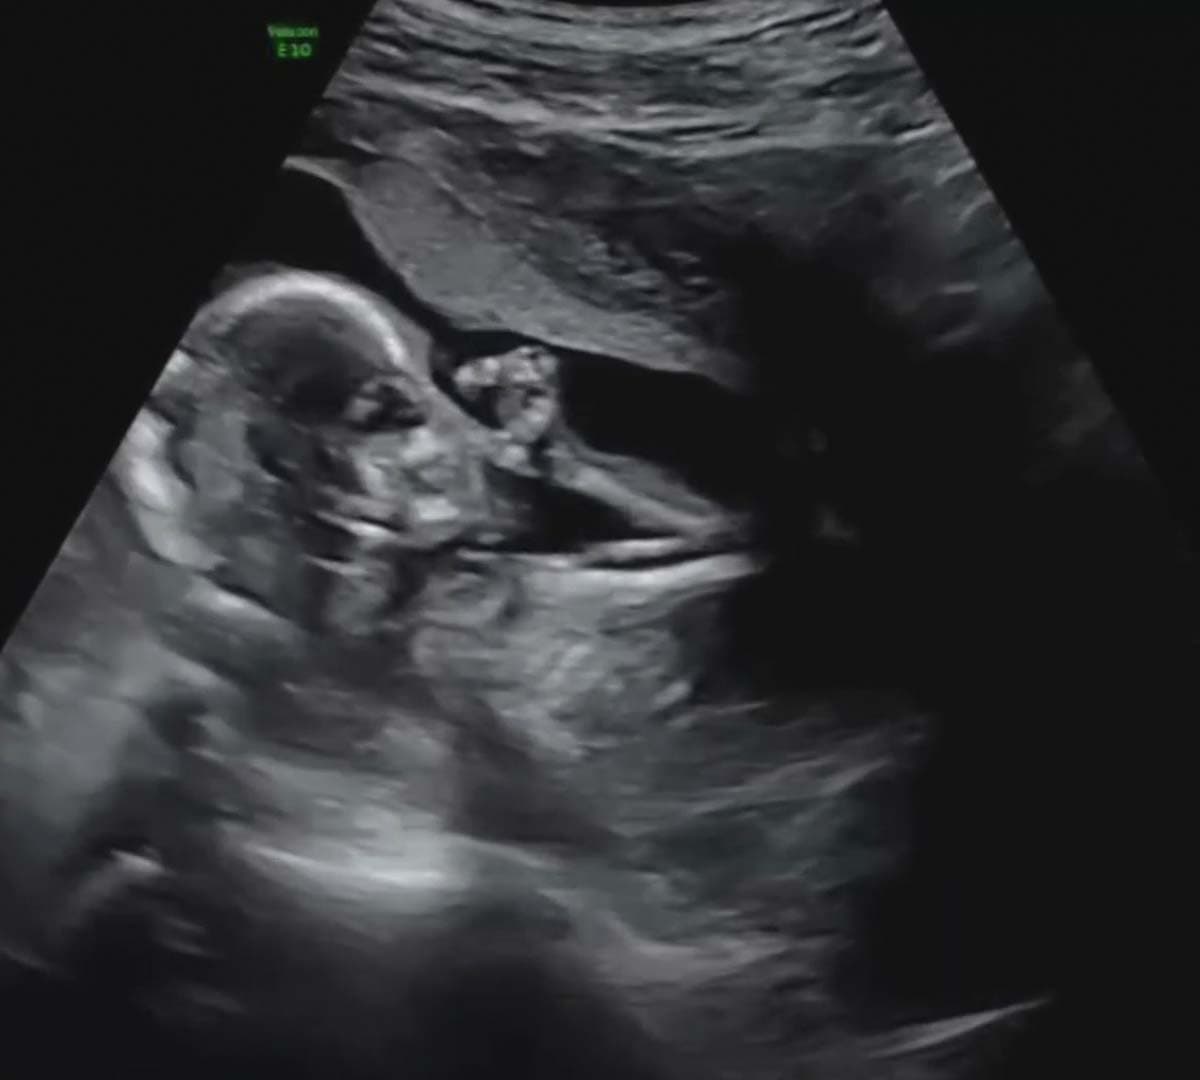

A inicios de noviembre pasado, Charry se realizó un ultrasonido en vivo en una de las emisiones de El Gordo y La Flaca, en donde se dio a conocer que un niño venía en camino.

‘’It’s a boy’ (Es un niño) Hoy en vivo en El Gordo y La Flaca el doctor Steve Rad nos dio la gran noticia que vamos a tener un niño. Sebastián, Zoe (y yo) estamos felices”, comentó en esa ocasión Tanya Charry junto al video del momento en Instagram.